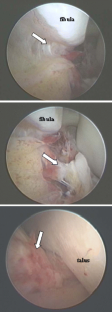

Fig. 1

Arthroscopic findings showed ATFL injury in 30 out of 34 cases. The diagnosis of ATFL injury with stress X-P, US, MR imaging were made with an accuracy of 67, 91 and 97%. US and MR imaging demonstrated the same location of the injury as arthroscopy in 63 and 93%.